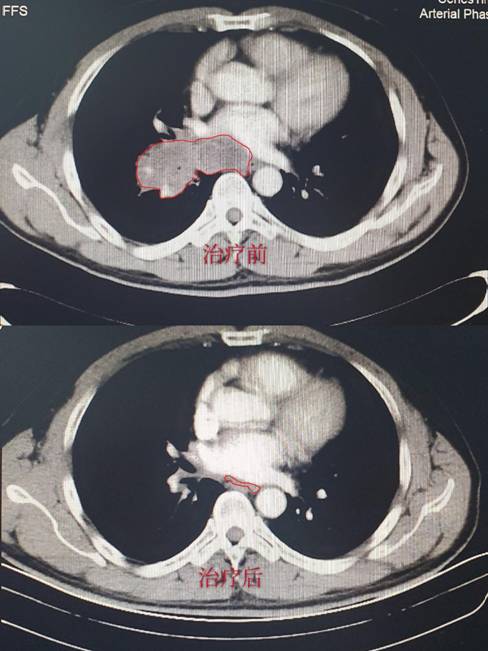

病例1:储某某,诊断为:左肺小细胞癌广泛期。经2周期治疗后复查胸部CT,肿瘤缩小达90%,肿瘤接近消失,达到很好的效果;(CT结果如下,红色线框内为肿瘤组织。)

病例2:应某某,诊断为:左肺小细胞癌广泛期。治疗之前存在严重咯血及咳嗽,治疗3天后就停止咯血,咳嗽明显好转,经 2周期治疗后免费复查胸部CT,肿瘤缩小80%。(CT结果如下,红色线框内为肿瘤组织。)